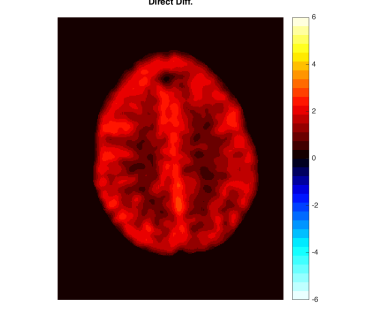

As a motivating example that will be detailed in Section 5, Figure 1 shows data from the phantom experiment in Qin et al., (2017) simulating pre- and post-treatment scans with a tumor lesion. A direct voxelwise difference between the two scans shows a global non-homogeneous background change while failing to detect changes in the lesion (Figure 1, Row 1 and Column 3). This observation suggests that background adjustment is necessary in voxelwise comparisons to reduce confounding by tissue-dependent changes not related to the disease, in order to isolate localized differences that are relevant to assess the disease status.

In the first half of this paper, we study the standardization of a Gaussian mixture model systematically in various but simple ways. We show that, surprisingly, the tail distribution of the standardized scores is favorably close to standard normal in a wide range of scenarios while being conservative at the tails, making it suitable for statistical inference. Compared to the standardization method for background adjustment in Guo et al., (2014) and Qin et al., (2017), we consider several variations using both soft and hard assignment of the observations to latent classes. In the data application in Figure 1, the analysis based on the model-based standardized differences proposed in this paper is successful (Row 2 and Column 3) as the background difference is now randomly distributed around zero and the lesion change is clearly visible; see Section 5 for more details. The distributions of the corresponding standardized scores are evaluated here theoretically, numerically and via simulations. Theoretically, it is shown that the standardized scores are indeed close to standard normal under a variety of extreme parameter settings. In non-extreme parameter settings, it is shown numerically that the soft assignment methods lead to conservative tail probabilities, making them valid for hypothesis testing purposes. It is also shown that the tail probabilities are not very sensitive to the class probabilities, which is an advantage as these are hard to estimate in practice.

In this section, we provide more details about the PET data application discussed in the Introduction (Figure 1). We use the data produced by the lesion change detection study in (Qin et al.,, 2017) using the Hoffman 3-D brain phantom (Hoffman et al.,, 1991), which simulates pre- and post-treatment scans with a tumor lesion. As described there, the brain phantom was filled with FDG radioactive fluid and PET scans were acquired on a GE Discovery ST PET-CT scanner. A malignant lesion was simulated within the central gray matter at a location superior and anterior within the brain, by placing a 1.5 cm diameter sphere of FDG. The tumor-to-background-ratio (TBR) for Scan 1 was 2:1, which was changed to 1.5:1 for Scan 2. Due to the physical construction of the phantom, these two TBR levels were achieved by increasing the activity in the phantom background rather than changing the activity in the lesion (injecting more radio-tracer to the background, while keeping the activity concentration in the lesion constant), effectively producing a reduction in the lesion activity with respect to the background. Image registration was performed between the two scans. The first row of Figure 1 shows one slice of the two scans and their difference (same slice as in Qin et al., (2017)).

By design, there is a large background change but no change in the lesion. A direct difference between the two scans shows a global non-homogeneous background change while failing to detect changes in the lesion (Figure 1, Row 1 and Column 3). In contrast, the analysis based on the model-based standardized differences proposed in this paper is successful (Figure 1, Row 2 and Column 3). Specifically, the second row shows the standardized scores using the proposed robust EM algorithm RB-SGMM and background adjustment via the soft-assignment transformation . The estimated background parameters are those given in (4.1). The standardized scores show a distribution close to standard normal with little anatomical structure except for the lesion. The standardized difference in the third column again has a distribution close to standard normal and exhibits the lesion change clearly at -6 standard deviations away from 0.